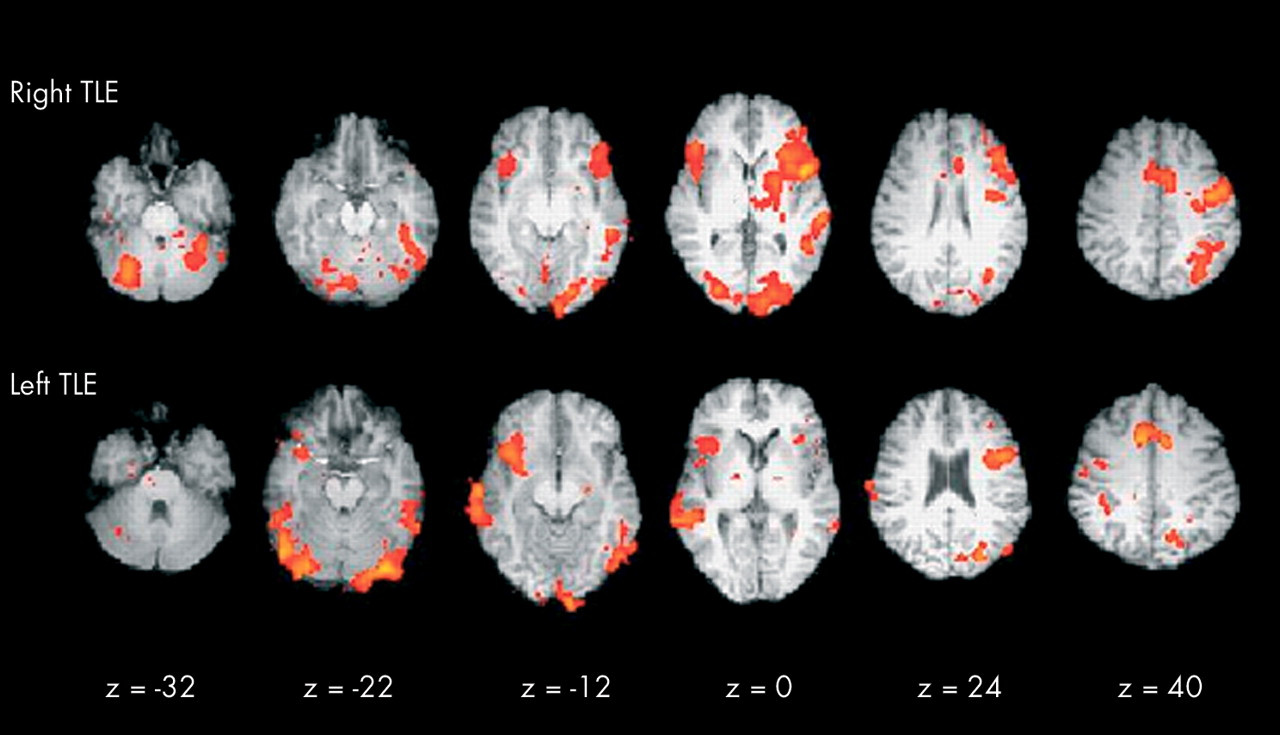

functional mri.jpg Review: neuroscience for neurologists, Functional magnetic resonance imaging, P M Matthews, P Jezzar

우리가 움직이려면 음식을 먹어야 하듯, 몸 안의 장기들도 작동하려면 영양을 공급받아야한다. 그 통로가 혈관이다 보니 뇌에서도 기능을 하는 부분으로 피가 많이 가게 되는 원리를 이용해 위와 같은 영상을 얻는다. 어떤 생각이나 행동을 하라고 한 다음 뇌 영상에서 특정 부분이 반응한다면 그 쪽은 그 기능을 담당하는 분야인 것이다. 혹은, 어느 부분을 다쳤을 때 특정 기능을 할 수 없다면 마찬가지로 적용될 수 있다.